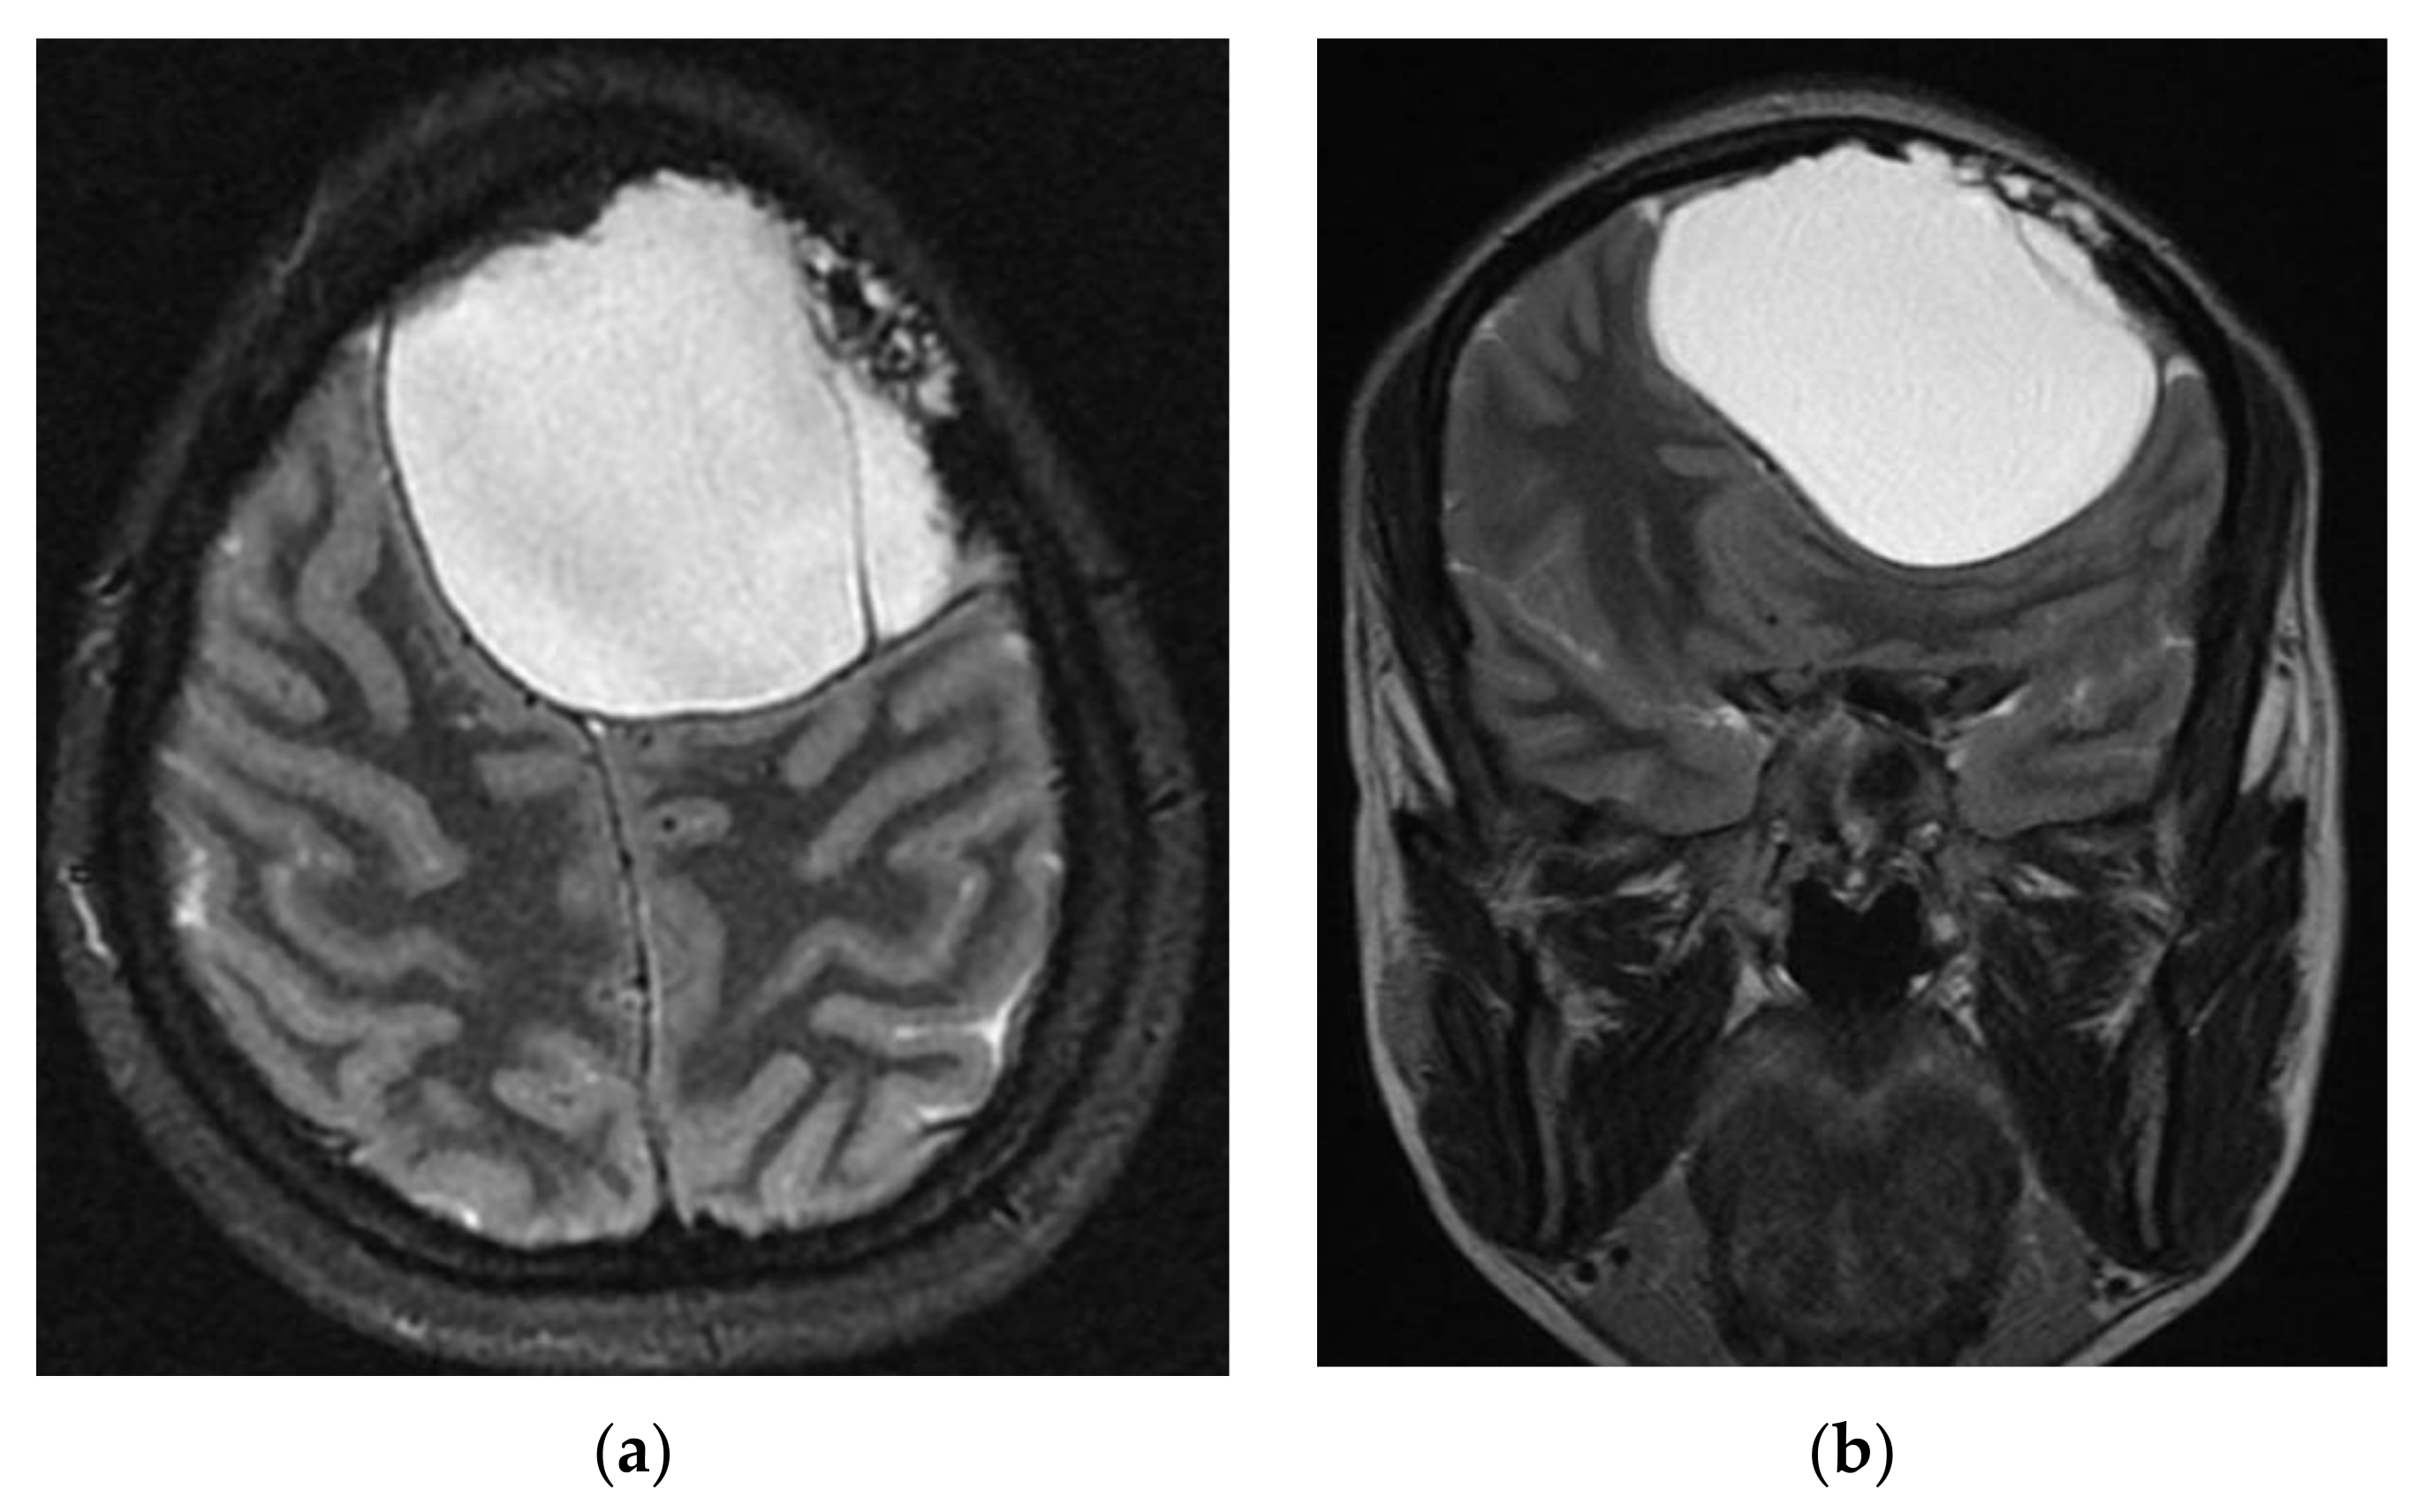

A head computed tomography (CT) Scan with intravenous (IV) contrast (Figure 2 and Figure 3) showed a huge left frontal cyst, with a fine wall and a fine septum inside, minimum peripheral load, left frontal osteolysis, moderate peripheral edema, edematous optic nerves (bilateral secondary papillary edema). Cranio-cerebral magnetic resonance imaging (MRI) examination with contrast (Figure 4) supported the diagnostic suspicion of a cerebral hydatid cyst. Cystic lesions with membranes and daughter cysts are highly probable to be hydatid ones [7]. Based on the morphology classification, this hydatid cyst was a type IIa: a cyst with round daughter cysts at the periphery [8].

The 6 months and 1 year follow-up showed no recurrence of cystic masses and no neurological deficit (Figure 11).

Figure 4. Cerebral magnetic resonance imaging (MRI) supports the diagnostic suspicion of intracerebral hydatid cyst: (a) axial; (b) coronal.

Figure 11. Twelve months follow-up CT Scan. (a) axial—very good left frontal lobe recovery. (b) 3D reconstruction.